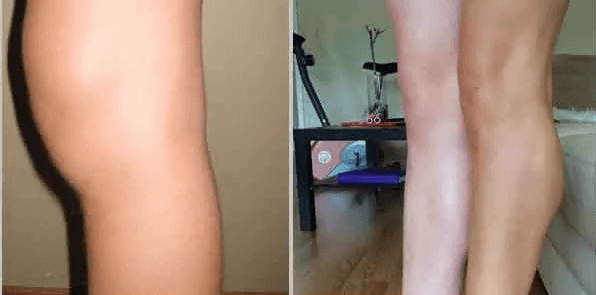

Zde jsou výsledky dosažené některými našimi pacienty:

Tento pacient měl revmatoidní artritidu kolena stupně 1. Jak vidíte, nemoc zmizela beze stopy. Po 5 dnech používání.

Typická kolenní artróza 2. stupně a její úplné vymizení po 7 dnech léčby.

Jedná se o 3. stupeň. Artróza malých prstů. Zotavení po prvním ošetření.